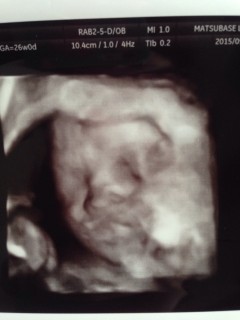

4人目です(*^^*)右手で右目をこすってるように見えるエコー写真です(*^^*)カナリ可愛くて先生からも、可愛い~!と言われました。男の子で体重998gで標準との事でした♪2週間後に会うのが楽しみ。